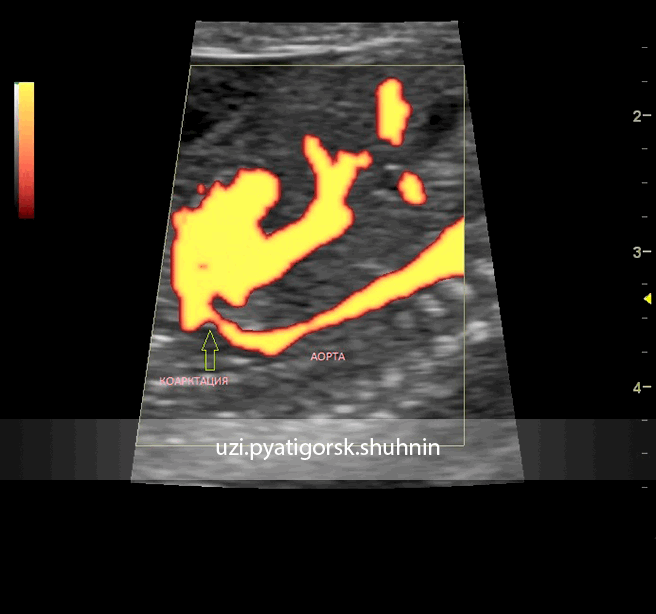

УЗИ, 2-й скрининг беременности. Режим ЭД. Отчетливо визуализируется участок коарктации (стрелка) дуги аорты. Установлен диагноз коарктации аорты.

Согласно "теории дуктальной ткани" коарктация аорты возникает в результате миграции гладких мышечных клеток протока в предуктальную аорту, с последующей констрикцией и сужением просвета аорты [4]. При формировании коарктации аорты в области перешейка сохраняется сужение различной протяженности и формы (рис. 2, 3). Наиболее часто это проявляется в виде локальной перетяжки, выше или ниже которой диаметр аорты сохраняется в норме.

Рис. 2. Ультразвуковое исследование восходящего отдела, дуги и нисходящего отдела аорты. Стрелкой указано место сужения.